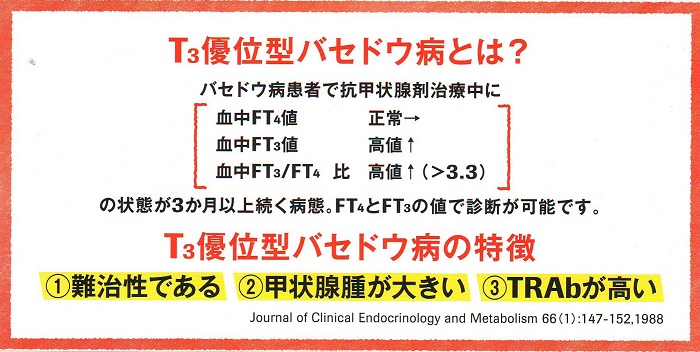

難治性T3優位型バセドウ病は、甲状腺組織の脱ヨード酵素(2型脱ヨード酵素:DIO 2)活性が異常に高いために、FT4に比してFT3が著明に高値になります。元々、甲状腺機能亢進症/バセドウ病はFT3が相対的に高いものですが、T3優位型バセドウ病では、さらに顕著なFT3/FT4比上昇になります。

T3優位型バセドウ病は、甲状腺機能亢進症/バセドウ病の約10%を占めるとされ、若年女性に多く、巨大甲状腺腫、TSH レセプター抗体(TRAb)異常高値が特徴。

薬物治療抵抗性で、再発を繰り返し、I-131 治療は1回で終わらず高用量I-131 を必要とし、結局、甲状腺全摘出手術になります。(Annals of Internal Medicine 1984 100 372–375.)(International Congress Series No. 605: 237-240, 1982.15)

T3優位型バセドウ病と気が付く時

T3優位型バセドウ病と気が付く時は

- 巨大甲状腺腫、TSH レセプター抗体(T-Ab)値が異常に高い

- 甲状腺超音波(エコー)検査で、下甲状腺動脈が異常に太く、下甲状腺動脈血流速度(ITA-PSV)が異常高値

- 薬物治療によりFT4正常化してもFT3が高値

- 薬物治療抵抗性で、再発を繰り返す